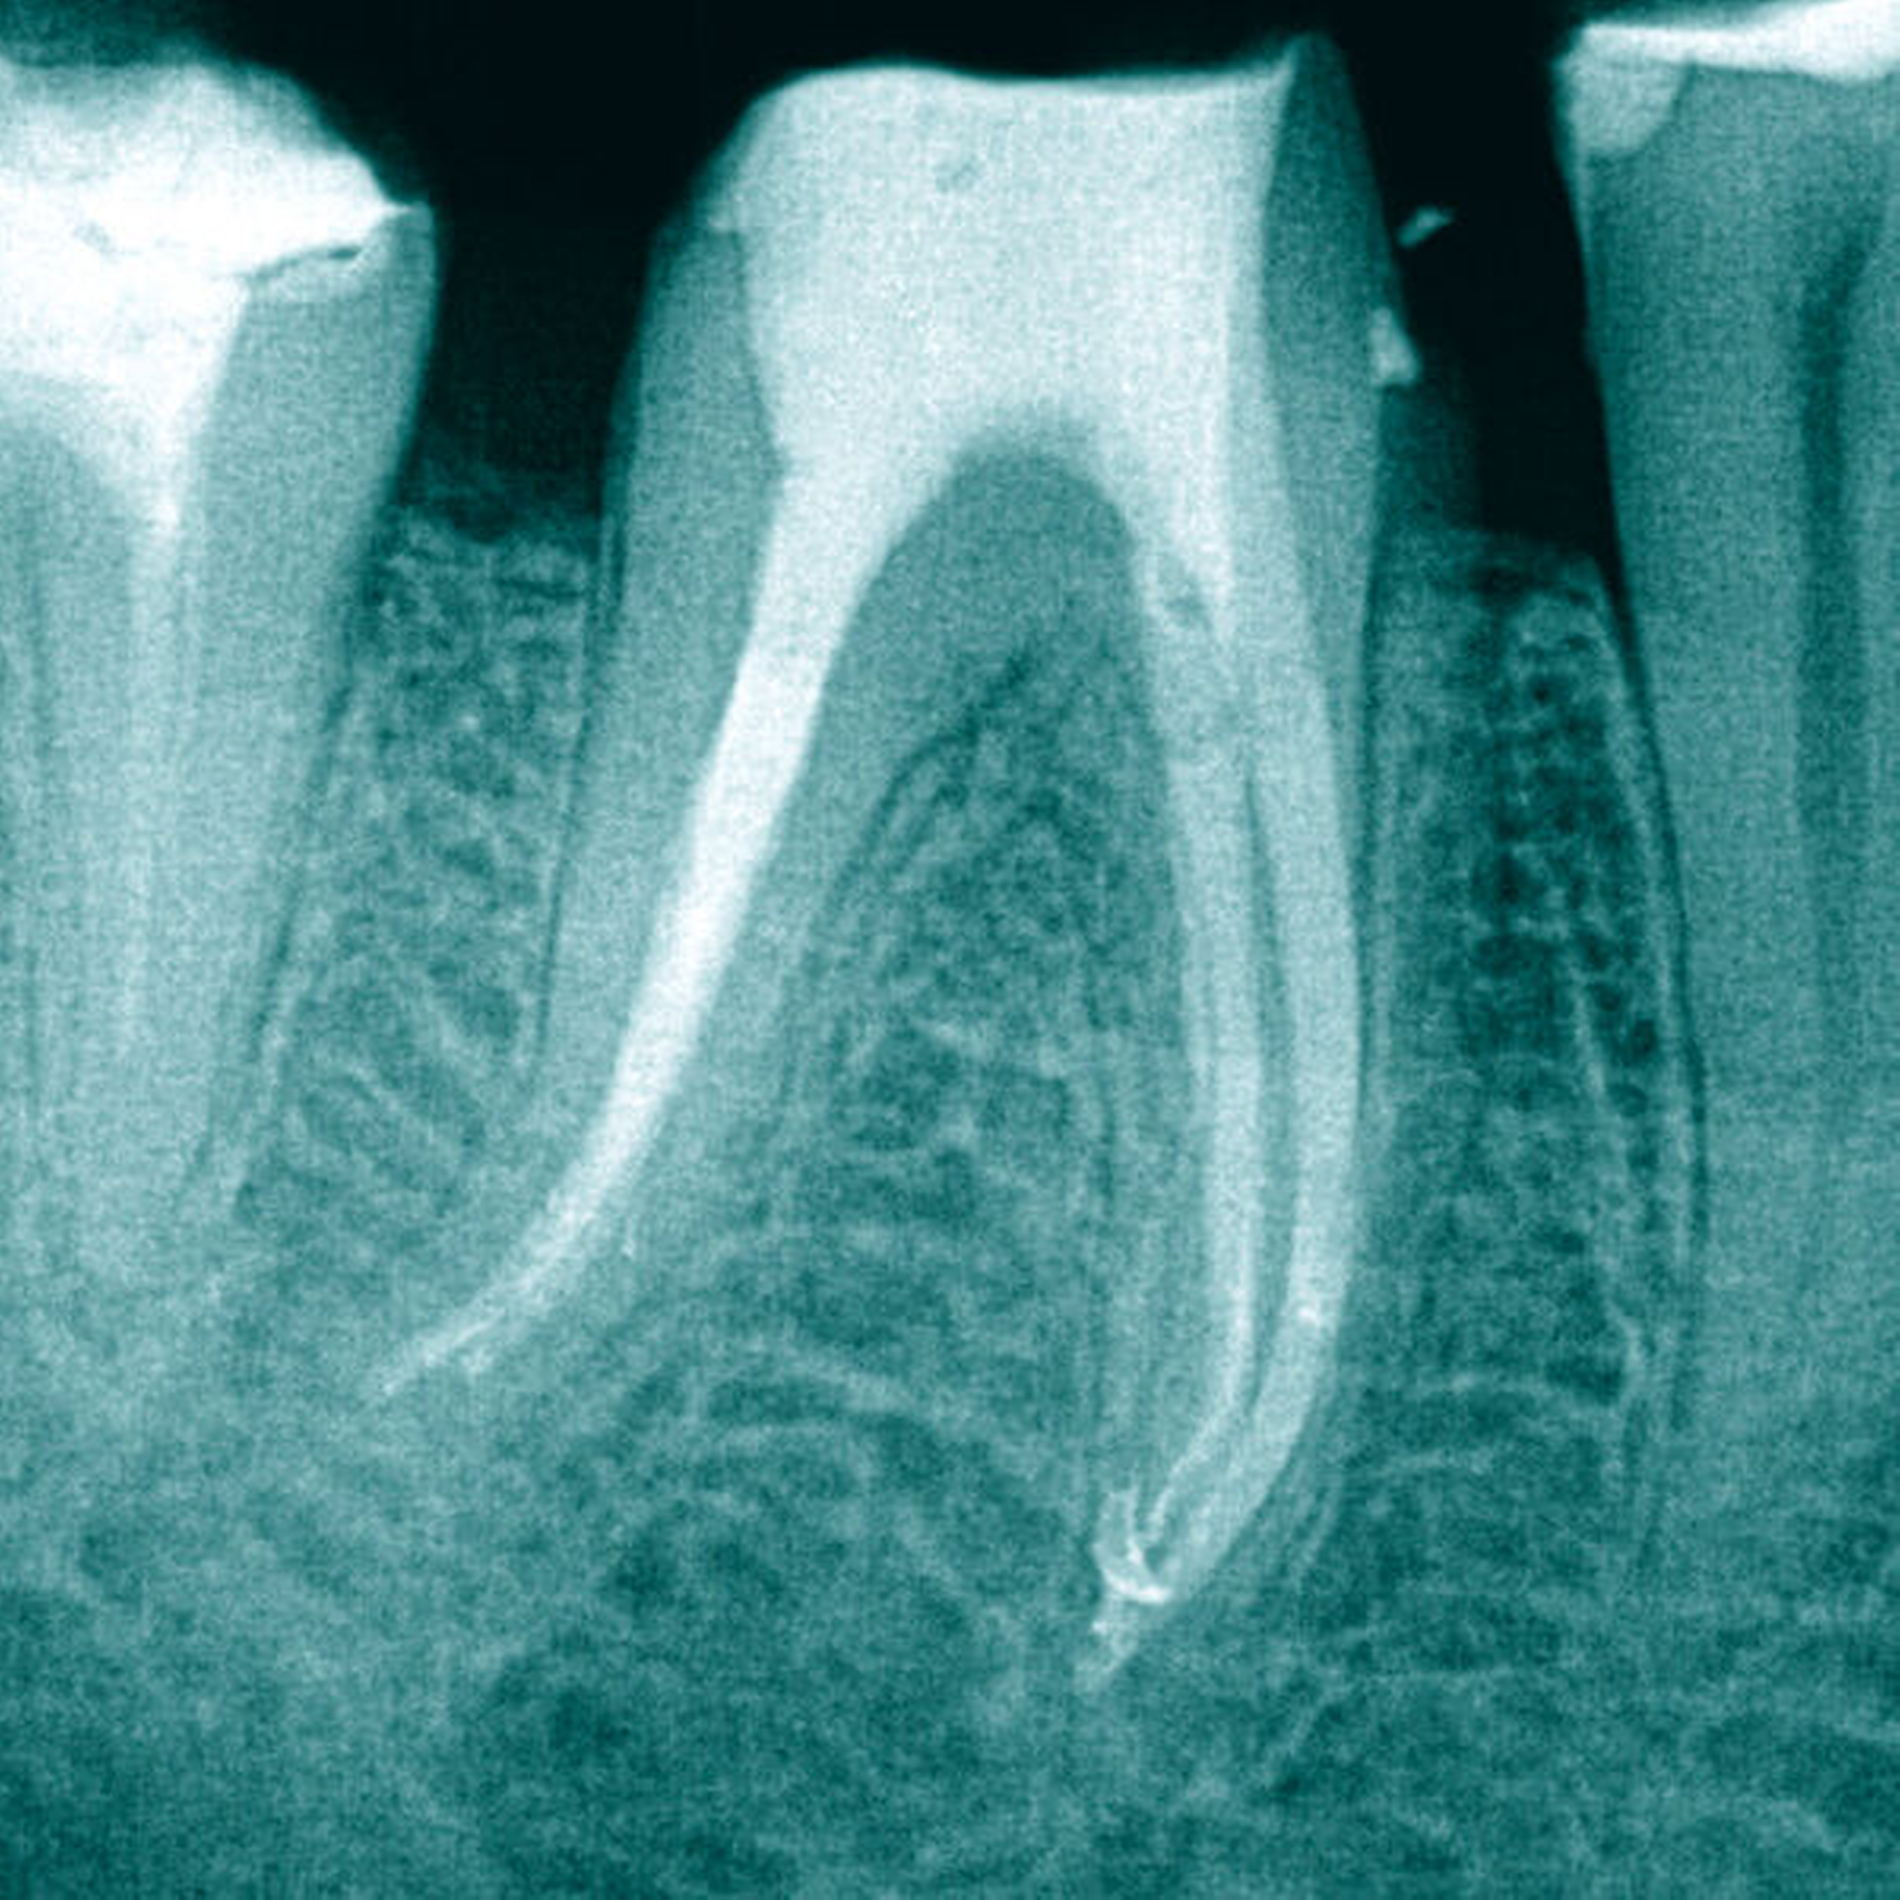

Das eingeschraubte Fragment wurde koronal mittels Ultraschalltechnik (VDW Ultra, VDW, München, Deutschland; Endo-Chuck, B&L Biotech, Fairfax, USA) 3 mm freigelegt und aufgerichtet. Anschließend konnte das Fragment mit der Tube-Dorn-Apparatur gegriffen und entfernt werden (Abbildung 4). Daraufhin wurde Durchgängigkeit in allen drei Wurzelkanälen erreicht und es erfolgte die chemomechanische Aufbereitung. In der nächsten Sitzung wurde die Obturation mit Guttapercha und AH Plus (Dentsply Sirona, York, USA) warm-vertikal modifiziert nach Schilder durchgeführt (Abbildung 5).